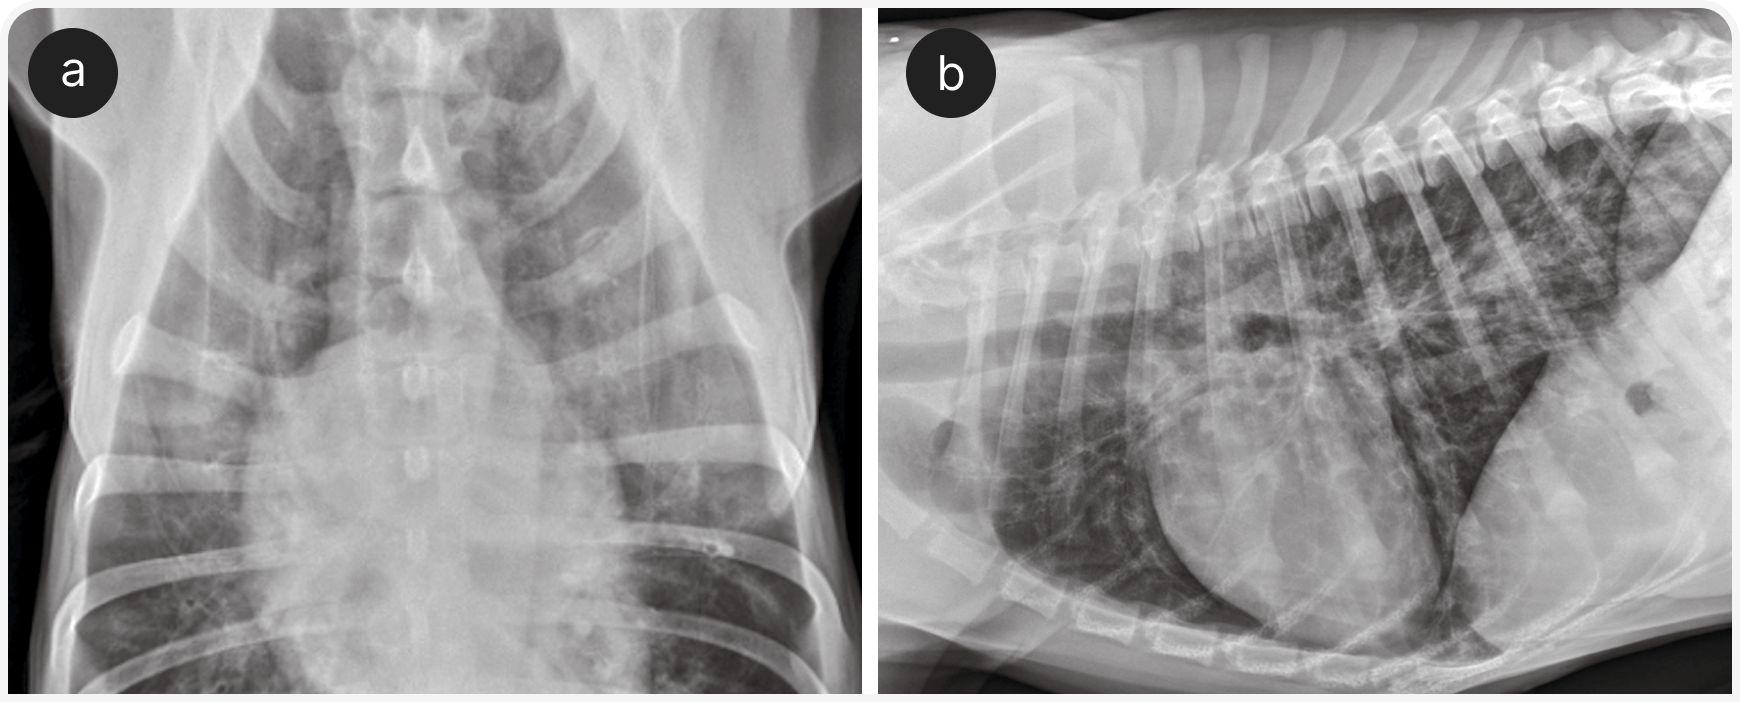

Этим пациентам могут быть полезны ингаляции кислорода и бронходилататоры, такие как тербуталин; однако у собак с подозрением на серьезные заболевания сердца следует соблюдать осторожность, так как тербуталин может увеличить частоту сердечных сокращений. После стабилизации рекомендуется провести рентгенографию органов грудной клетки для выявления картины бронхиального или бронхоинтерстициального поражения (Рисунок 2), хотя диагностическая чувствительность рентгенографии при заболеваниях бронхов у собак относительно низкая (2).

В таких случаях следует рассмотреть дальнейшее диагностическое обследование, такое как эндотрахеальный или транстрахеальный лаваж с цитологическим исследованием смывов. Можно провести рентгеноскопию, бронхоскопию или компьютерную томографию для выявления динамического коллапса трахеи и/или главного бронха (если их не выявили при рентгенографии), объемных или узелковых образований в трахее, бронхоэктазов или избыточной выработки слизи.

Результаты этих исследований при заболеваниях нижних дыхательных путей могут соответствовать друг другу относительно слабо, поэтому в идеале их применяют в комбинации (3, 4). Наконец, для диагностики инфекции легочной нематодой можно использовать фекальный тест Берманна, хотя часто предпочитают эмпирически назначить лечение фенбендазолом. При подозрении на бронхит может быть рекомендовано снизить дозу кортикостероидов; некоторые специалисты на длительный прием предпочитают назначать флутиказон ингаляционно, чтобы уменьшить системное всасывание и побочные эффекты.